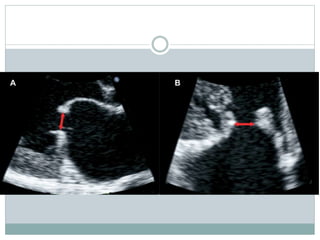

Mitral leaflet separation (MLS) index

 Distance between the tips of the mitral leaflets in

parasternal long-axis and four-chamber views

 it can be used as a semiquantitative method for the

assessment of MS severity

 A value of 1.2 cm or more provided a good specificity

and PPV for the diagnosis of non severe MS

 less than 0.8 cm -severe MS.

 It is not accurate in patients with heavy mitral

valvular calcification and post BMV